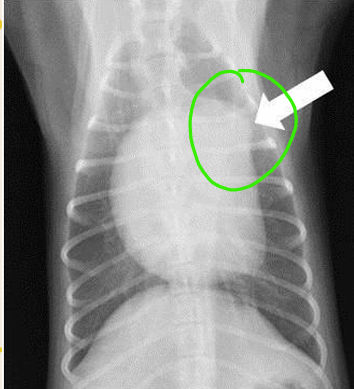

DV

arrow pointed the THYMUS